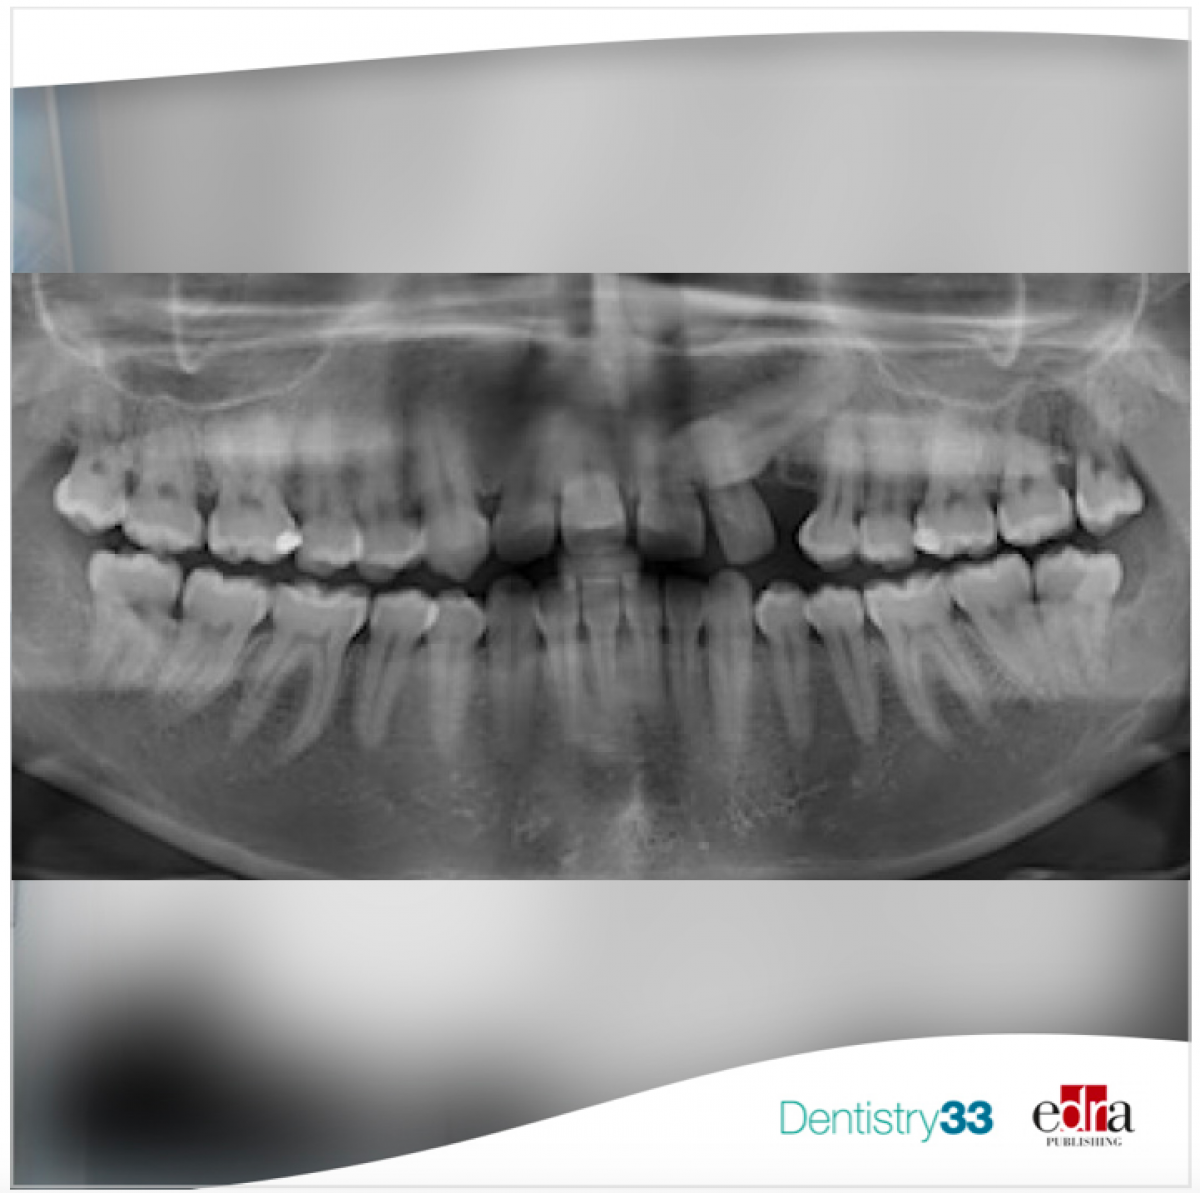

The maxillary canines usually emerge at the mean age of 10.5 years in girls and 11.5 years in boys, with individual variation of 3–4 years. In 2–3 per cent of the Caucasian population, these teeth fail to erupt and become impacted, which is defined as obstruction by hard or soft tissue structures and/or an ectopic eruption pattern.

The aetiology of the impacted canines is obscure and probably. Early preventive measures in the mixed dentition for palatal canine impaction are desirable, due to the risk of root resorption of the neighbouring permanent incisors. Such resorptions have been reported to occur in 47 per cent of subject in the age range of 10–13 years. However, a considerable variation in diagnostic tools, study designs, sample sizes, and research approach has produced results and conclusions that are sometimes conflicting and may be difficult to compare and interpret.

In the issue of November of The Angle Orthodontist, an article was published to investigate whether extracting the primary canine and primary first molar was more beneficial than extracting only the primary canine in improving the emergence rate of PDCs (palatally displaced canines). Thirty-two children aged 9.5–13.5 years with 48 PDCs were randomly allocated to either the double-extraction group (DEG) or single-extraction group (SEG). Clinical and radiographic examinations were performed at baseline and at 6-month intervals until the canine emerged or orthodontic treatment was started.

As results, no significant difference was observed between groups. Significant predictors of canine emergence were initial canine angulation and space conditions at the beginning of treatment.

To conclude, double or single primary tooth extraction procedures are equivalent in supporting PDC eruption into the oral cavity and into a favorable position in the dental arch. Initial canine angulation and space assessments may be used as predictors of successful PDC eruption.